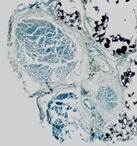

Axon counts overall were found to be higher, in general, for the ORIF group (186, SD = 73.0) than the NON group (145, SD = 44.6), but this did not reach statistical significance (P=0.24). None of the subgroups reached statistical significance in direct comparisons. Images of a sciatic nerve from the nonsurgical leg, an ORIF leg, and a NON ORIF leg, all at 12 weeks postoperative, are shown in Figures 1, 2, and 3, respectively.